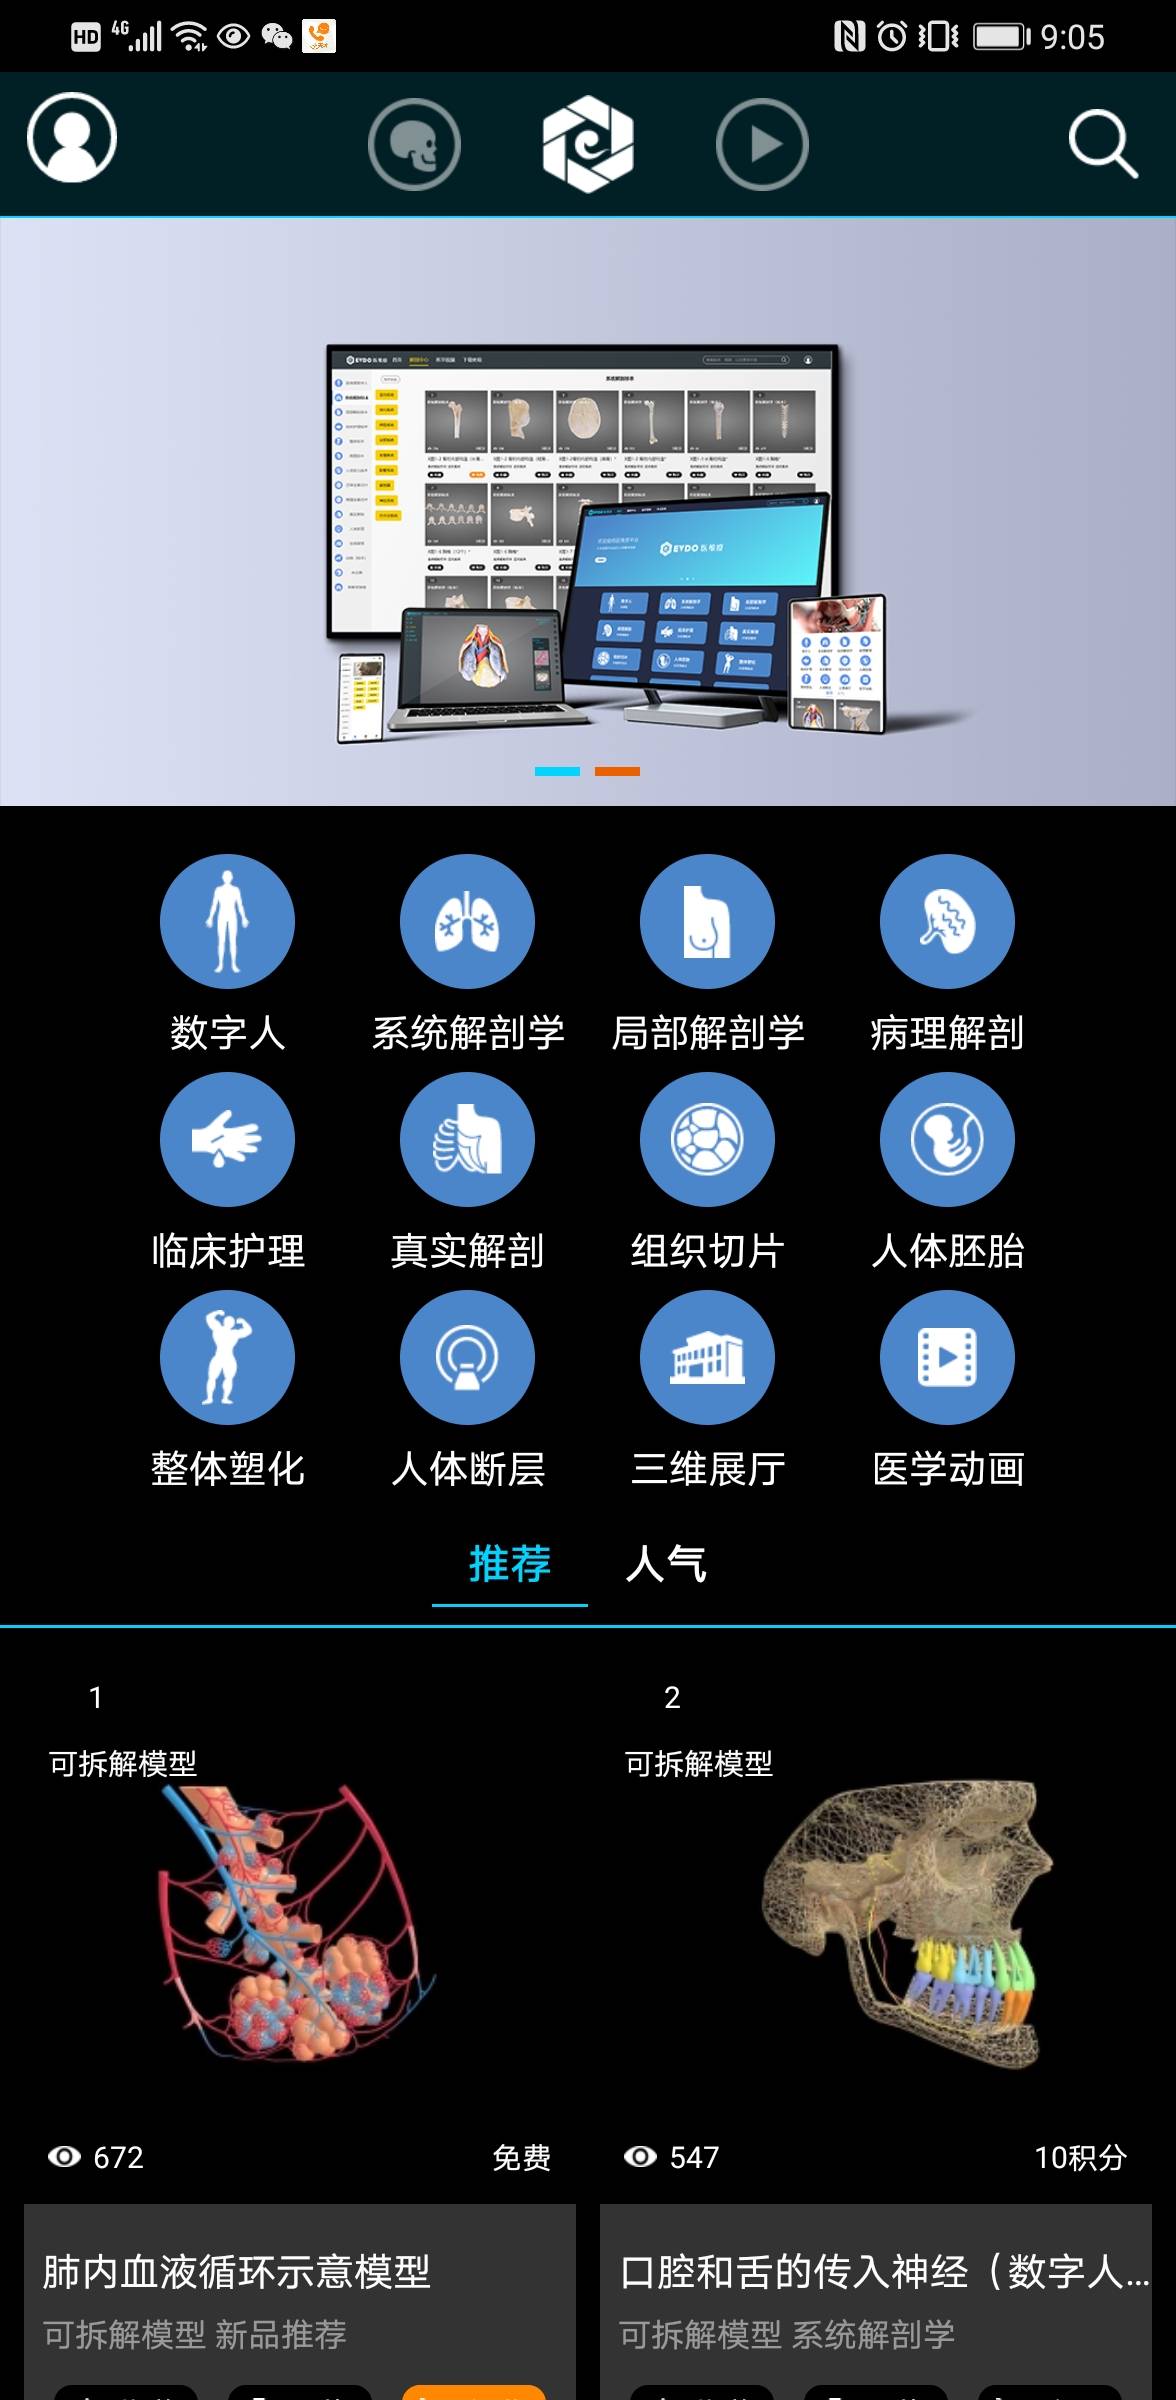

医维度人体解剖软件是一款专为医学教育和临床学习设计的高精度三维人体解剖软件,它提供了详尽的人体结构展示和互动学习功能,帮助用户深入理解人体解剖知识。

该软件结合了最新的三维建模技术和医学影像学数据,确保所有解剖结构的高精度还原,为用户提供逼真的学习体验。

用户普遍反映,医维度人体解剖软件的操作界面简洁直观,易于上手,极大地提高了学习效率。

许多用户称赞该软件的三维模型精细度高,能够清晰地展示人体各个部位的细节结构,有助于深入理解解剖知识。

软件内置的互动学习功能,如旋转、缩放、标注等,让用户能够自由探索人体结构,增强了学习的互动性和趣味性。